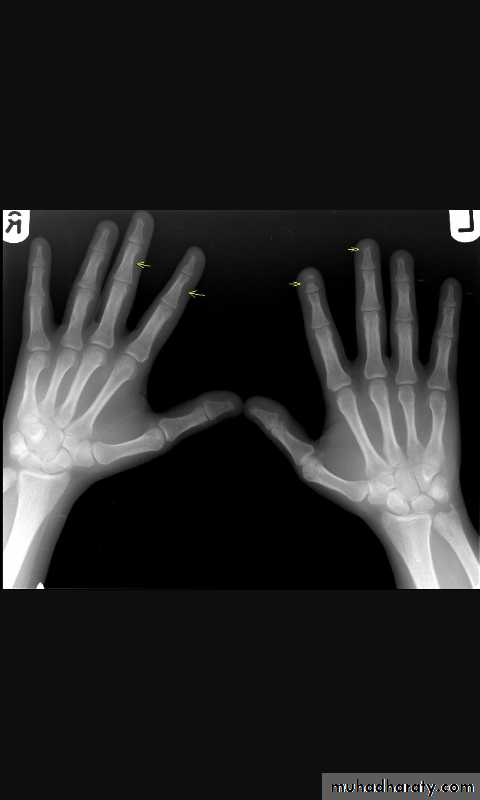

Skeletal X-rays:

Normal in early disease

Demineralization

Subperiosteal erosions and terminal resorption of phalanges

Salt and paper appearance on lat. skull x-ray

Osteopenia and osteoporosis by DEXA